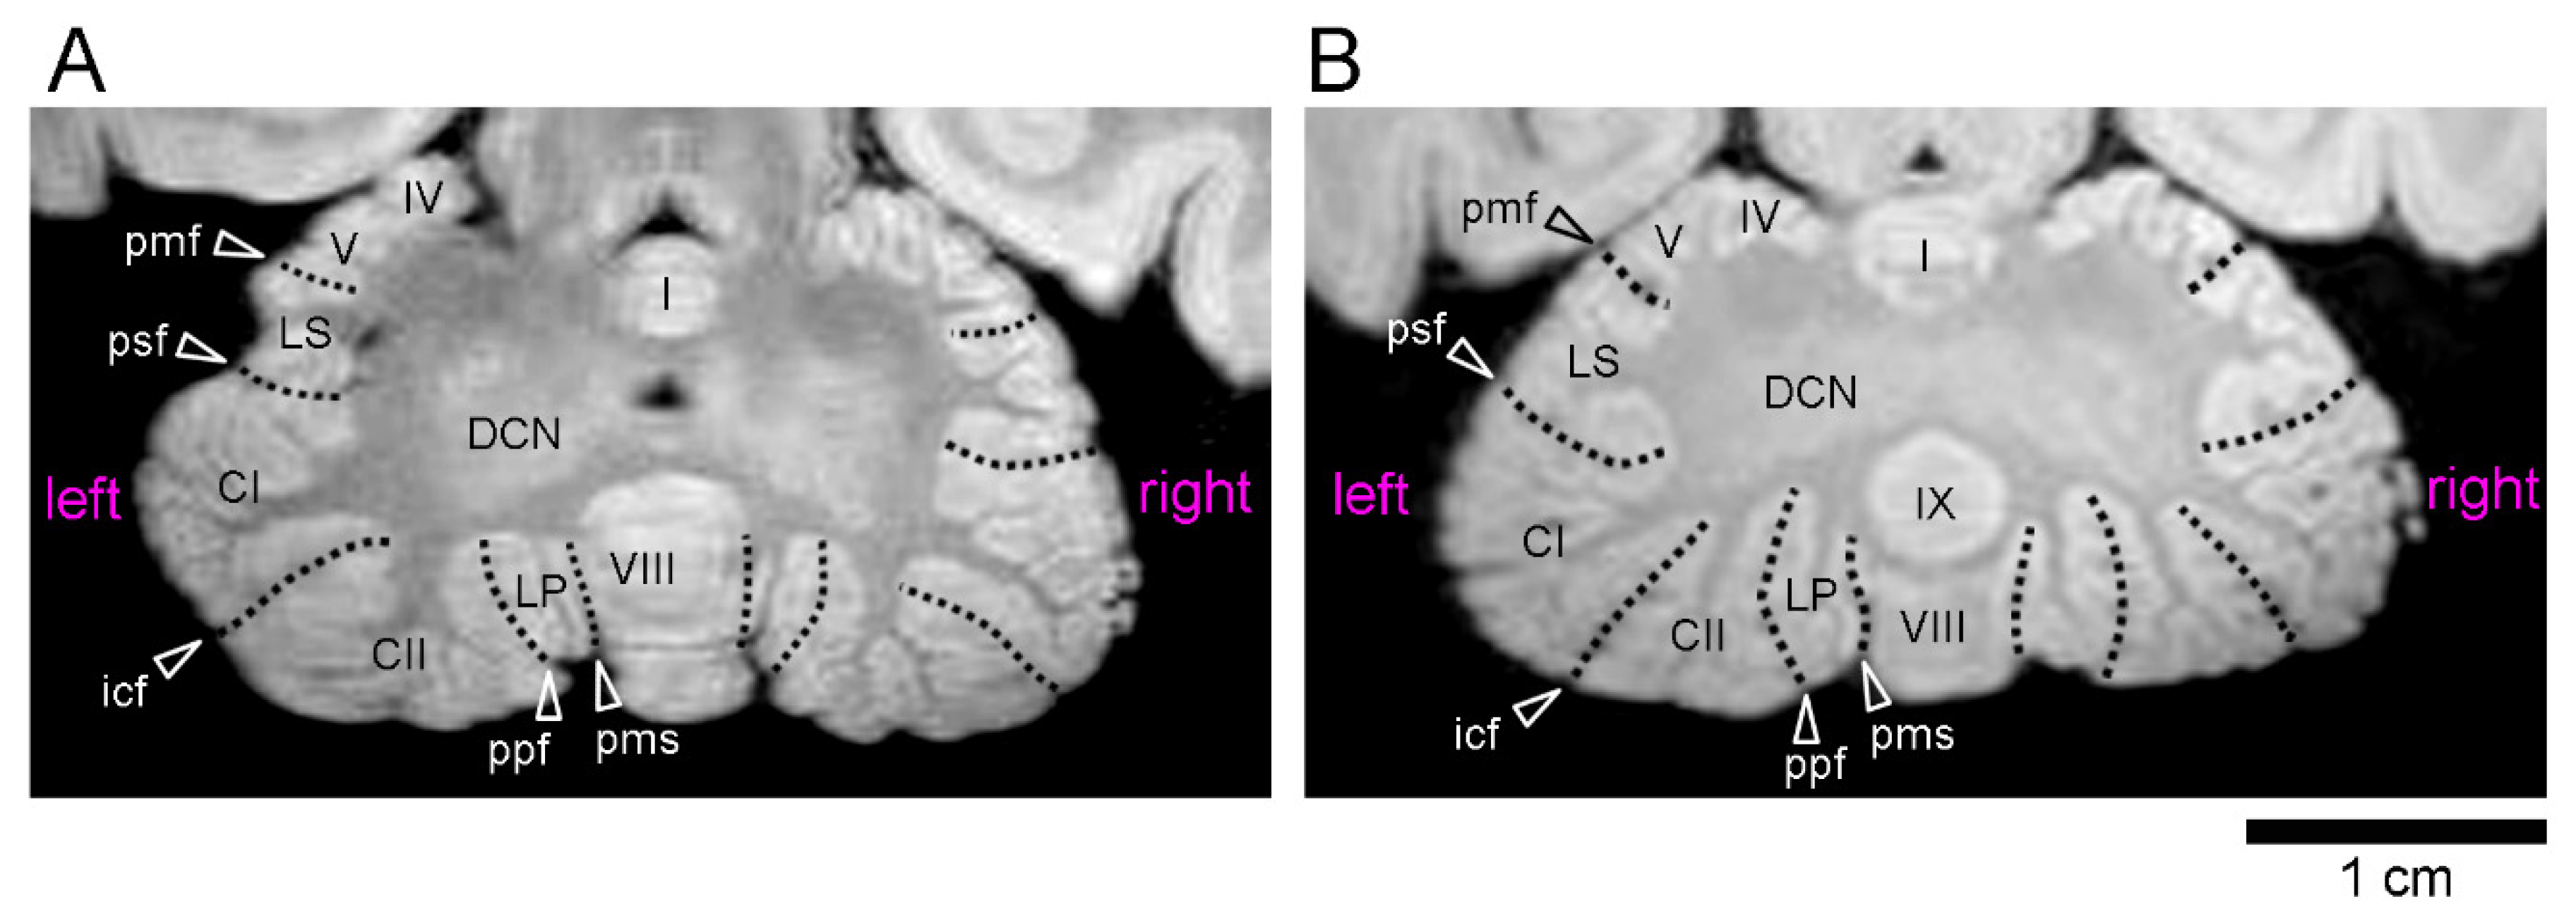

Figure 2.

Ex vivo MR images (using a RARE sequence with a short TR and the minimum TE settings) of cerebella through the deep cerebellar nuclei in young adult cynomolgus monkeys. (A) Axial MR image of the male cerebellum. (B) Axial MR image of the female cerebellum. Abbreviations are posted at the left side. Roman numerals identify the vermal lobules. CI—crus I of ansiform lobule; CII—crus II of ansiform lobule; DCN—deep cerebellar nuclei; icf—intercrucial fissure; LP—paramedian lobule; LS—lobulus simplex; pmf—primary fissure; pms—paramedian sulcus; ppt—prepyramidal fissure; psf—posterior superior fissure.

The volumes of the five cerebellar transverse domains were compared between the left and right sides. Repeated-measures three-way ANOVA revealed significant effects in the left/right sides [F(1,8) = 9.282; p < 0.05], cerebellar transverse domains [F(4,32) = 195.805; p < 0.001], and an interaction between the left/right sides and cerebellar transverse domains [F(4,32) = 9.282; p < 0.01]. Following significant simple main effects, the paired sample t-test indicated significantly larger volumes on the left side than on the right side in the CZp of the males (p < 0.01) and in the AZ of the females (p < 0.01) (Table 3). Notably, a significant left bias of the male CZp volume (p < 0.05), but not the female AZ volume, was detected at the population level by the one-sample t-test (Table 3). We further calculated the volumes of the left/right of the cerebellar hemispherical lobules in the CZp (crura I and II), PZ (paramedian lobule), and NZ (flocculus and paraflocculus) regions. The repeated measures three-way ANOVA revealed significant effects on the left/right sides [F(1,8) = 5.614; p < 0.05] and in the cerebellar hemispherical lobules [F(3,24) = 27.861; p < 0.001]. A significantly larger volume was detected in male crus II regions on the left side compared to on the right side, as determined by the paired sample t-test (p < 0.05) (Table 4), following a significant simple main effect (p < 0.01). A significant left bias indicated by AQ values in the male crus II region volumes was revealed at the population level by the one-sample t-test (p < 0.01) (Table 4). This left-lateralization of the male crus II region could be confirmed optically on MR images (Figure 2).